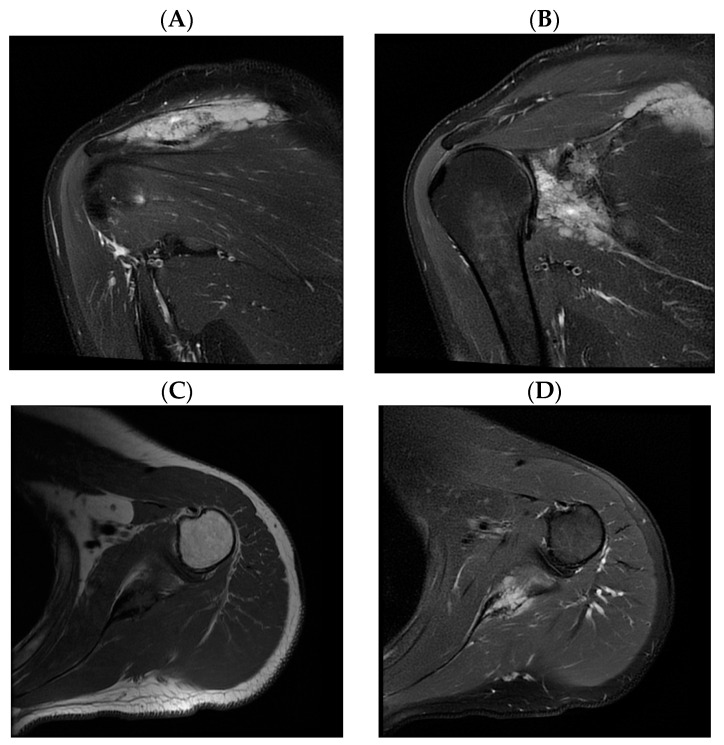

Primary bone lymphoma of the scapula is a rare tumor that usually causes local pain. The presented patient suffered for two years from paresthesia, tingling, numbness, and edema of the little and ring fingers. The 45-year-old man underwent several radiological and neurological assessments of the palm, elbow, and neck before radiographs revealed a tumor of the left shoulder. Once diffuse large B-cell lymphoma was confirmed, immunochemotherapy with rituximab, cyclophosphamide, doxorubicin, vincristine, and methylprednisolone (R-CHOP) started. The treatment was accompanied by antiviral treatment with lamivudine due to positive hepatitis B virus serology, specifically anti-HBs (hepatitis B surface) antibody, total anti-HBc (hepatitis B core) antibody, and anti-HBe (hepatitis B e antigen) antibody, together with bisphosphonate treatment for the prevention of bone resorption. Once immunochemotherapy was finished, the treatment was supplemented by radiotherapy of the shoulder. After more than three years of remission, the patient had an ischemic stroke manifesting with right-sided hemiparesis. Following physical therapy, the patient is currently in the process of evaluation for thrombophilia, as well as further cardiac assessment due to the positive transcranial Doppler bubble test, setting high suspicion for the presence of patent foramen ovale.